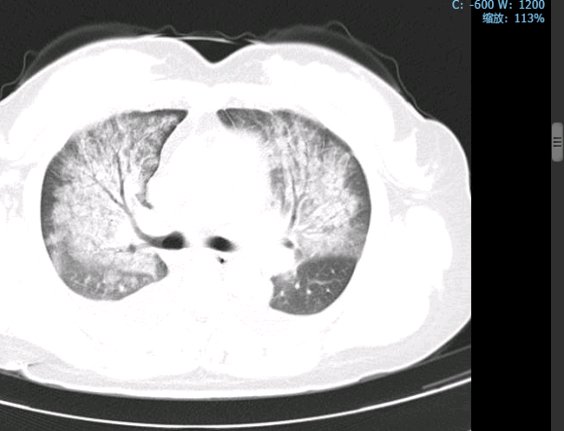

入院急查胸部CT显示:双肺见多发、弥漫性感染性病变,伴实变,累及肺间质,后进行详细查体时发现典型焦痂。

治疗前胸部CT

2天后实验室结果回报:血液宏基因组测序(mNGS)检出恙虫病东方体,特异性序列34条,置信度高。至此诊断明确,病原体与临床预判相符。经上述方案治疗12天后,复查胸部CT显示肺部病灶明显吸收,患者病情显著改善,最终顺利康复出院。